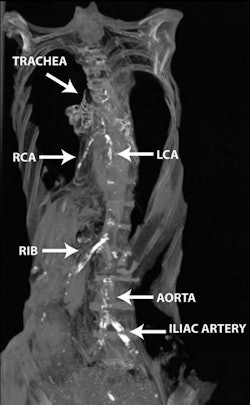

The study team scanned 178 consecutive modern Egyptian patients, all of whom had been referred by their primary physicians for cancer staging with PET at the Alfa Scan Outpatient Radiology center in Cairo. All patients were scanned on a Gemini TF PET/CT scanner (Philips Healthcare) in a single session from the base of the skull to the knee. Images were acquired using 1-mm slices and an average time interval of 0.8 msec. Interpretation consisted of searching for vascular calcifications in different vascular beds.

These results were compared with whole-body CT scans of 76 Egyptian mummies (3100 B.C.E. to 364 C.E.) scanned for the 2011 publication on a six-detector-row Emotion 6 scanner (Siemens Healthcare). Five experienced cardiovascular imaging physicians among the Horus investigators (who also performed the living human study) looked for cardiac and vascular calcifications in the carotid, coronary, aortic, iliofemoral, and peripheral vascular beds. Mummy selection was based on the specimens being in a good state of preservation rather than on random selection, the study team noted.

In both ancient and modern populations, "vascular calcification starts at the peripheral vascular bed (iliofemoral then aortic beds), then spreads to the target vessels (coronary and carotid beds) around a decade later than the onset of aortoiliac calcification," the authors wrote. There was also a trend toward higher incidence of vascular calcification among female mummies, but not modern Egyptians. Allam and colleagues hypothesized that the women may have been exposed to household smoke.